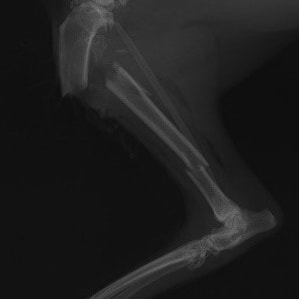

症例3:キルシュナーワイヤーのピンニングによる整復

ペルシャ猫 11ヶ月齢 雄

他院にて左大腿骨遠位の成長板骨折(salter-harrisⅠ型)が認められており、治療相談を目的として来院。当院にて、キルシュナーワイヤーを用いたピンニングにより骨折部位の整復を行いました。術後の経過は良好で、現在も経過観察中です。

術前レントゲン

術後レントゲン

機器

Arthrex社のターゲティングデバイスを用いてピンニングの位置を調整することで、確実な固定を行っています。当院ではこの手術器具以外にも、人の手術にも使用される様々な器具を導入し、手術精度を高め、また医療メーカーと新しい器具の開発、試作にも取り組んでおります。